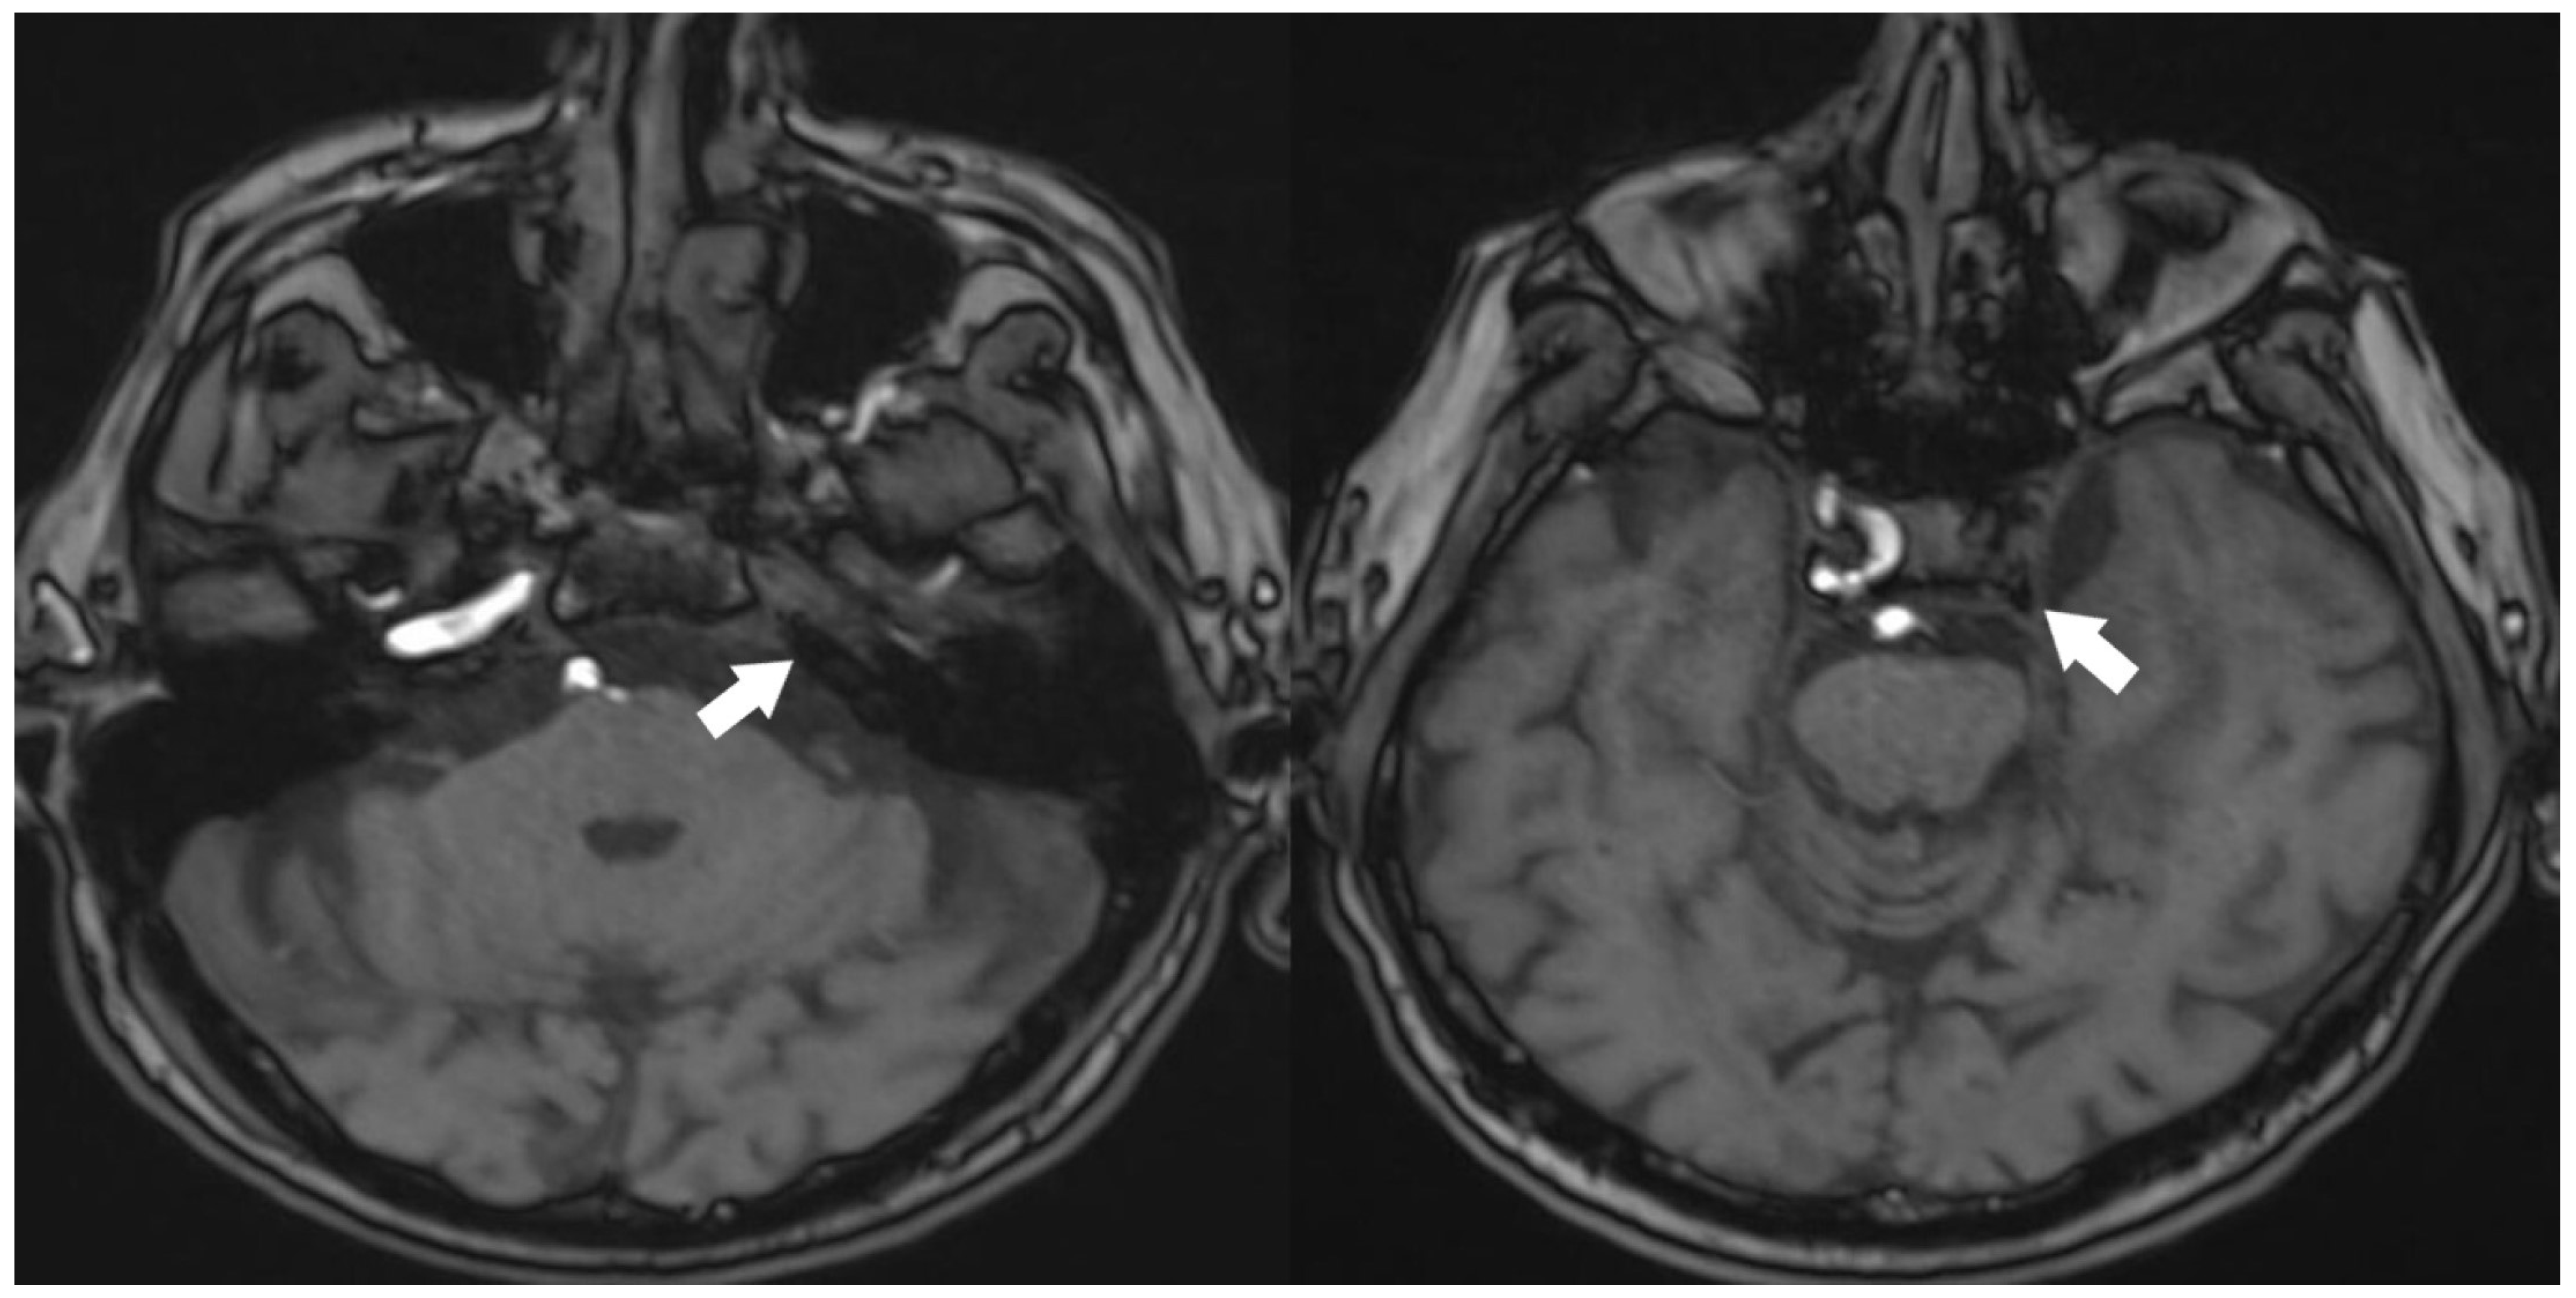

A 70-year-old male patient has presented with ongoing complaints of headache [VAS scale 6], pulsatile tinnitus [TFI level 3], and occasional dizziness. Neurological examination has revealed intact cranial nerves, bilaterally normal cerebellar function, normal deep tendon reflexes, a negative Romberg test, and preserved muscle strength. No abnormalities have been detected in other systemic examinations. Laboratory investigations showed no remarkable abnormalities. However, prior laboratory records indicated dyslipidemia for which the patient was under treatment, and he also had a known history of primary hypertension. Cranial MRI and MR angiography have demonstrated an absence of flow in the left internal carotid artery (Figure 1 and Figure 2).

Figure 2.

TOF 3D imaging of cranial MRI angiography [White arrow: no contrast filling in the carotid artery].

The anterior circulation has been supplied via the anterior communicating artery, while the posterior circulation has received perfusion through the posterior communicating artery (Figure 3).

Figure 3.

Anterior communicating artery [Red arrow] and posterior communicating artery [Yellow arrow], along with the vascular supply to the left hemisphere [TOF images].